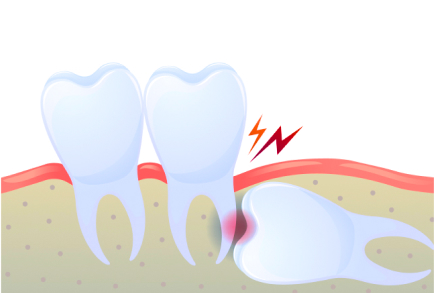

사선으로 자라 반은 잇몸안에 매복되어 있고

반은 잇몸 밖으로 나온 사랑니로

다른 치아에 손상을 입힐 수 있어 발치가 필요합니다.

안쪽에 있는 어금니의 뿌리가 흡수 될 수도 있고

다른 치아의 치열이 뒤틀릴 수 있어

발치가 필요합니다.